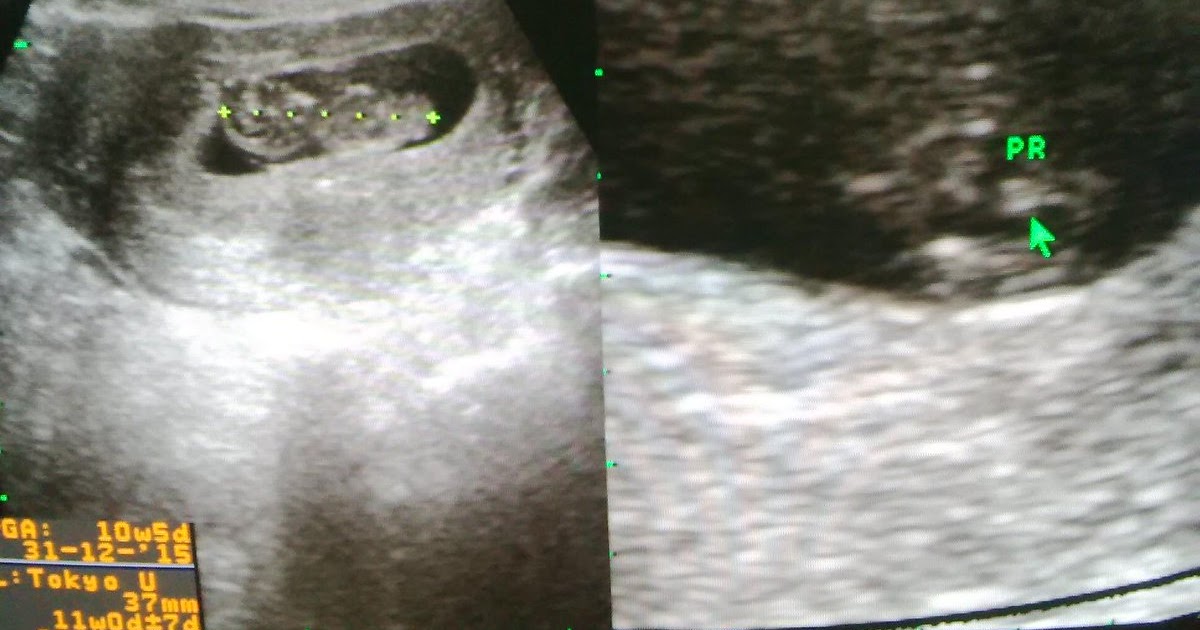

Gambar Hasil Usg Janin Perempuan : Mar 21, 2018 · gambar 1.